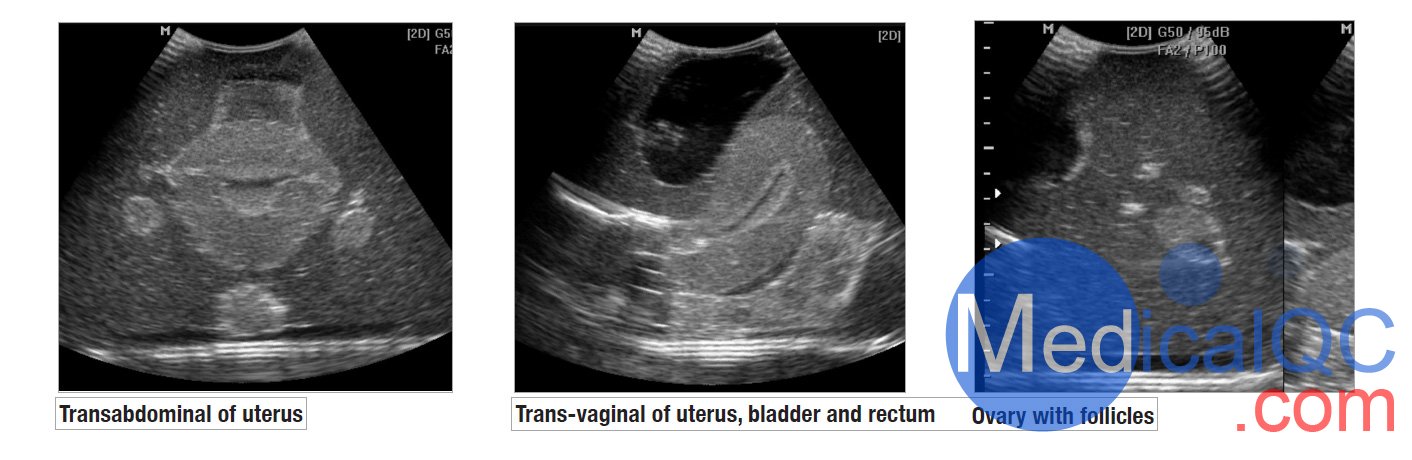

404A超聲訓練骨盆模體是一種重要的診斷工具。學生通過動手實踐獲得能力。不幸的是,接觸患者可能受到限制。CIrs 404A女性盆腔模體,CIrs 404A超聲訓練骨盆模體有助于在無壓力情況下教授和演示婦科超聲技術。

我們的CIrs 404A女性盆腔模體,CIrs 404A超聲訓練骨盆模體由一個外部女性盆腔模型組成,其中包含用于掃描的子宮、輸卵管、卵巢、膀胱和直腸標志。體模具有腹部和陰道掃描通道,允許各種換能器方向。

女性超聲訓練骨盆為教授和發展超聲檢查技能和技術以及展示 3D 超聲能力創造了一個輕松的學習環境。

CIrs 404A超聲訓練骨盆模體超聲影像圖:

CIrs 404A女性盆腔模體,CIrs 404A超聲訓練骨盆模體影像圖